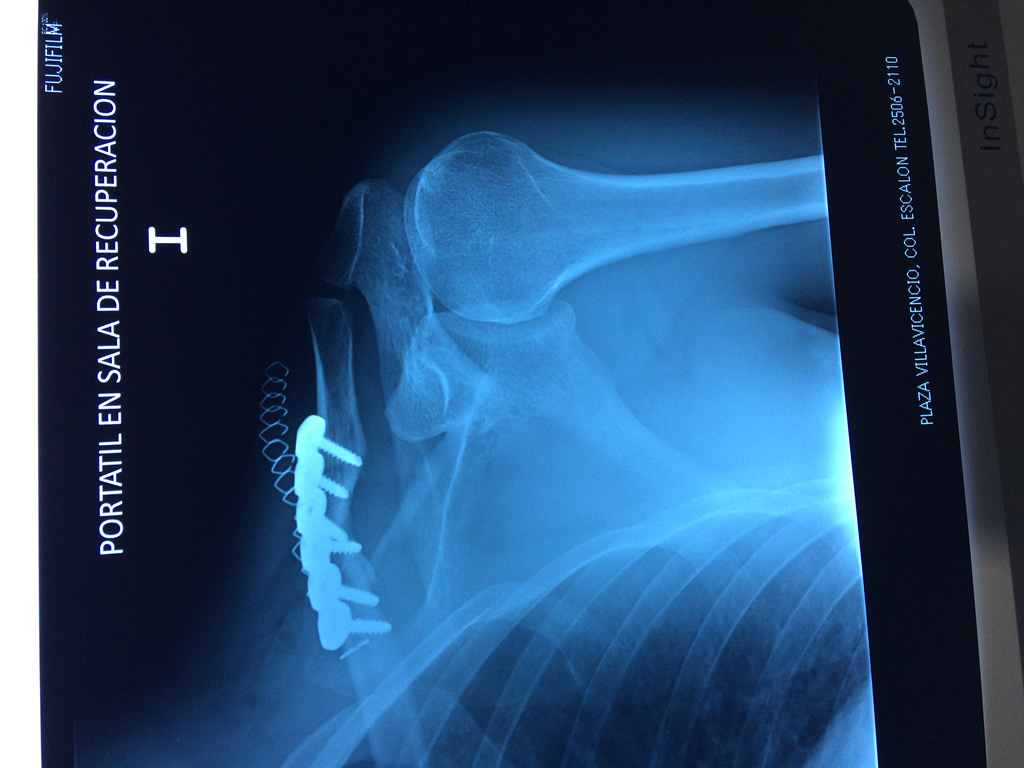

Cirugías de Codo - Clavícula

La clavícula es un hueso largo, con forma de "S" itálica, situado en la parte anterosuperior del tórax. Junto con la escápula forman la cintura escapular. Se puede palpar por toda su longitud y se extiende del esternón al acromion de la escápula, siguiendo una dirección oblicua lateral y posterior.